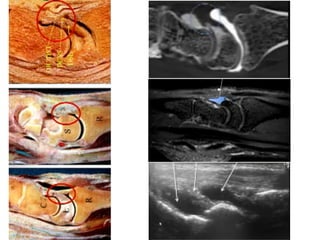

This presentation discusses various topics related to the wrist including static scapholunate ligament dissociation, dorsal ganglion cysts originating from the dorsal capsulolunate septum, treatment of scaphoid pseudarthrosis using a bone graft from the distal radius placed under the extensor tendons, and proximal pole scaphoid pseudarthrosis treated with capitolunate arthrodesis. It also thanks attendees and provides instructions for accessing the presentation online.